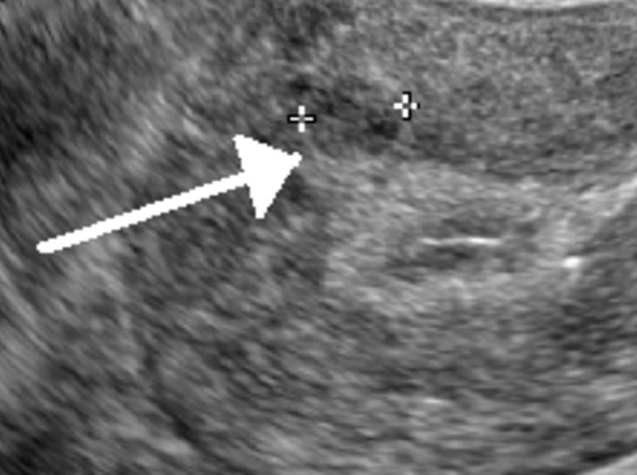

Leiomyomatous Uterus Ultrasound

The most effective way to image uterine fibroids is through transvaginal ultrasonography. When it comes to the diagnosis of this disease, its detection sensitivity ranges somewhere between 90 to 99 percent. Saline-infused sonography is an advancement in ultrasound technology that increases the sensitivity of the test for detecting subserosal and intramural fibromas. Fibroids look like a firm, well-defined, hypoechoic mass. Ultrasound examinations in these areas typically reveal varying degrees of shadowing and echogenicity distortion from calcifications or necrosis.